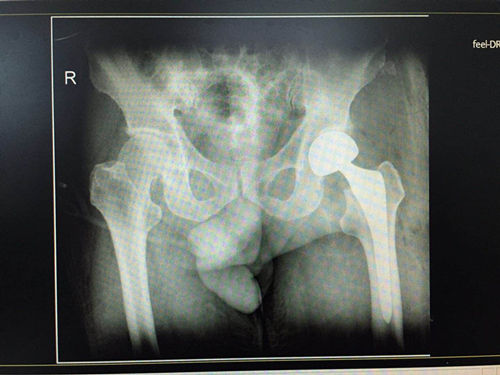

近日,骨一科成功为一位71岁前列腺癌中晚期老人实施人工股骨头置换手术。目前老人恢复良好,目前负重行走。

上报科室后,在翁润民主任的协调下,针对患者的治疗进行全院会诊,多学科认为患者心肺功能差、低蛋白血症等全身情况差,手术风险较大。医务科刘韬科长、医疗安全科贾京波科长对此患者高度重视,亲自给予患者家属充分沟通后,最终决定采用先行下腔静脉滤器置入降低围手术期新的血栓风险,随后行人工股骨头置换手术对老人进行救治。最后由程福宏副主任医师,郭张宏主治医师成功为老人实施了人工股骨头置换手术。手术顺利,但此患者故事仍在继续。